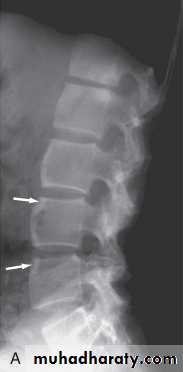

In established AS, radiographs of the sacroiliac joint show irregularity and loss of cortical margins, widening of the joint space and subsequently sclerosis, joint space narrowing and fusion.

Lateral thoracolumbar spine Xrays may show anterior ‘squaring’ of vertebrae due to erosion and sclerosis of the anterior corners and periostitis of the waist.

Bridging syndesmophytes may also be seen. These are areas of calcification that follow the outermost fibres of the annulus

Investigations

In advanced disease, ossification of the anterior longitudinal ligament and facet joint fusion may also be visible. The combination of these features may result in the typical ‘bamboo’ spine.